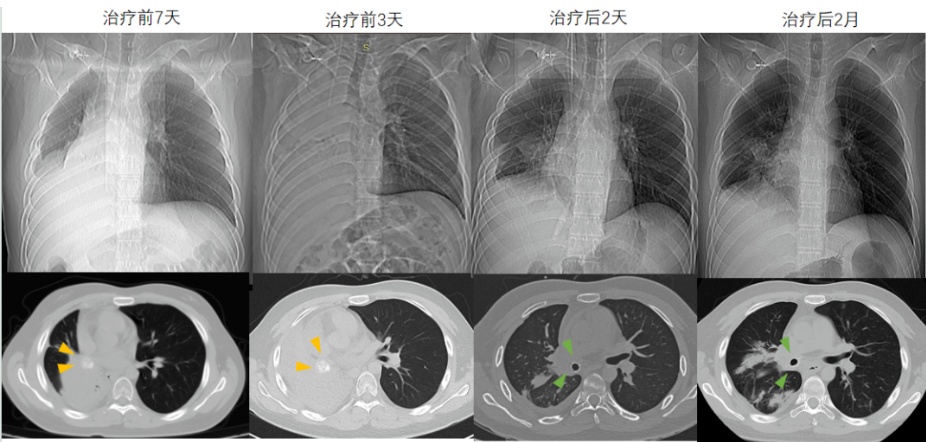

12天生死逆转!20岁小伙突然变 "大白肺"命悬一线,瑞金团队这样破局→

能想象吗?20岁小伙的整个右肺,在短短几天内像被戳破的气球,完全“塌”了下去,从CT上看,变成了一片毫无生气的“大白肺”!这不是电影情节,是男生小洋(化名)在瑞金医院经历的真实生死劫。幸运的是,在骨科、放射介入科、呼吸与危重症医学科、重症医学科等多学科专家12天的联手抢救下,“消失”的肺重新“鼓”了起来,年轻的生命得以重启。